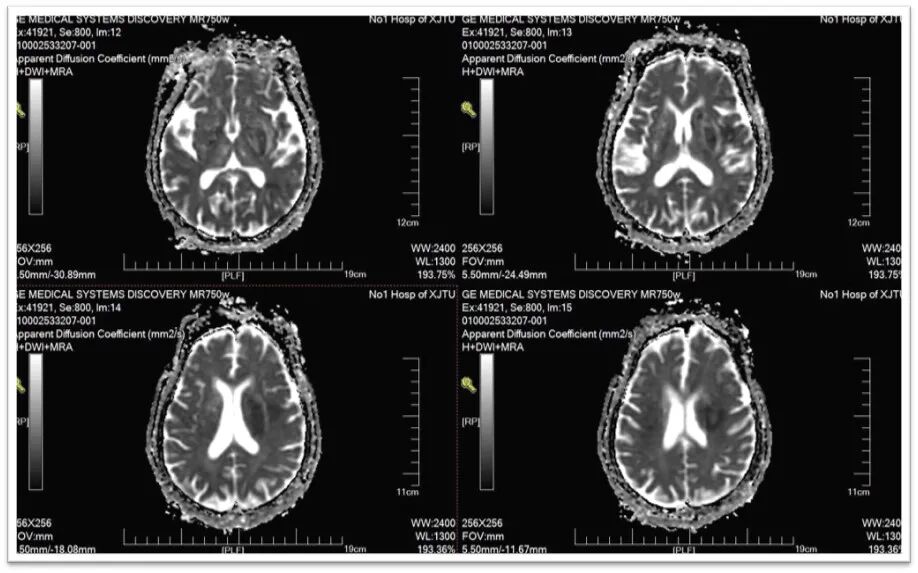

图2:头颅DWI提示左侧侧脑室旁基底节区新鲜脑梗死;

图3:头颈部MRA提示左侧颈总动脉闭塞,右侧双干大脑前动脉,左侧后交通动脉未开放;